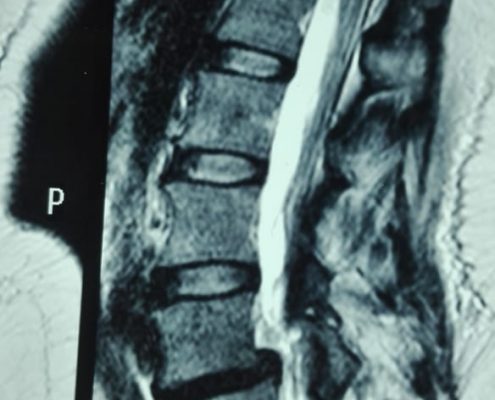

Latest Spine Fixation Technique